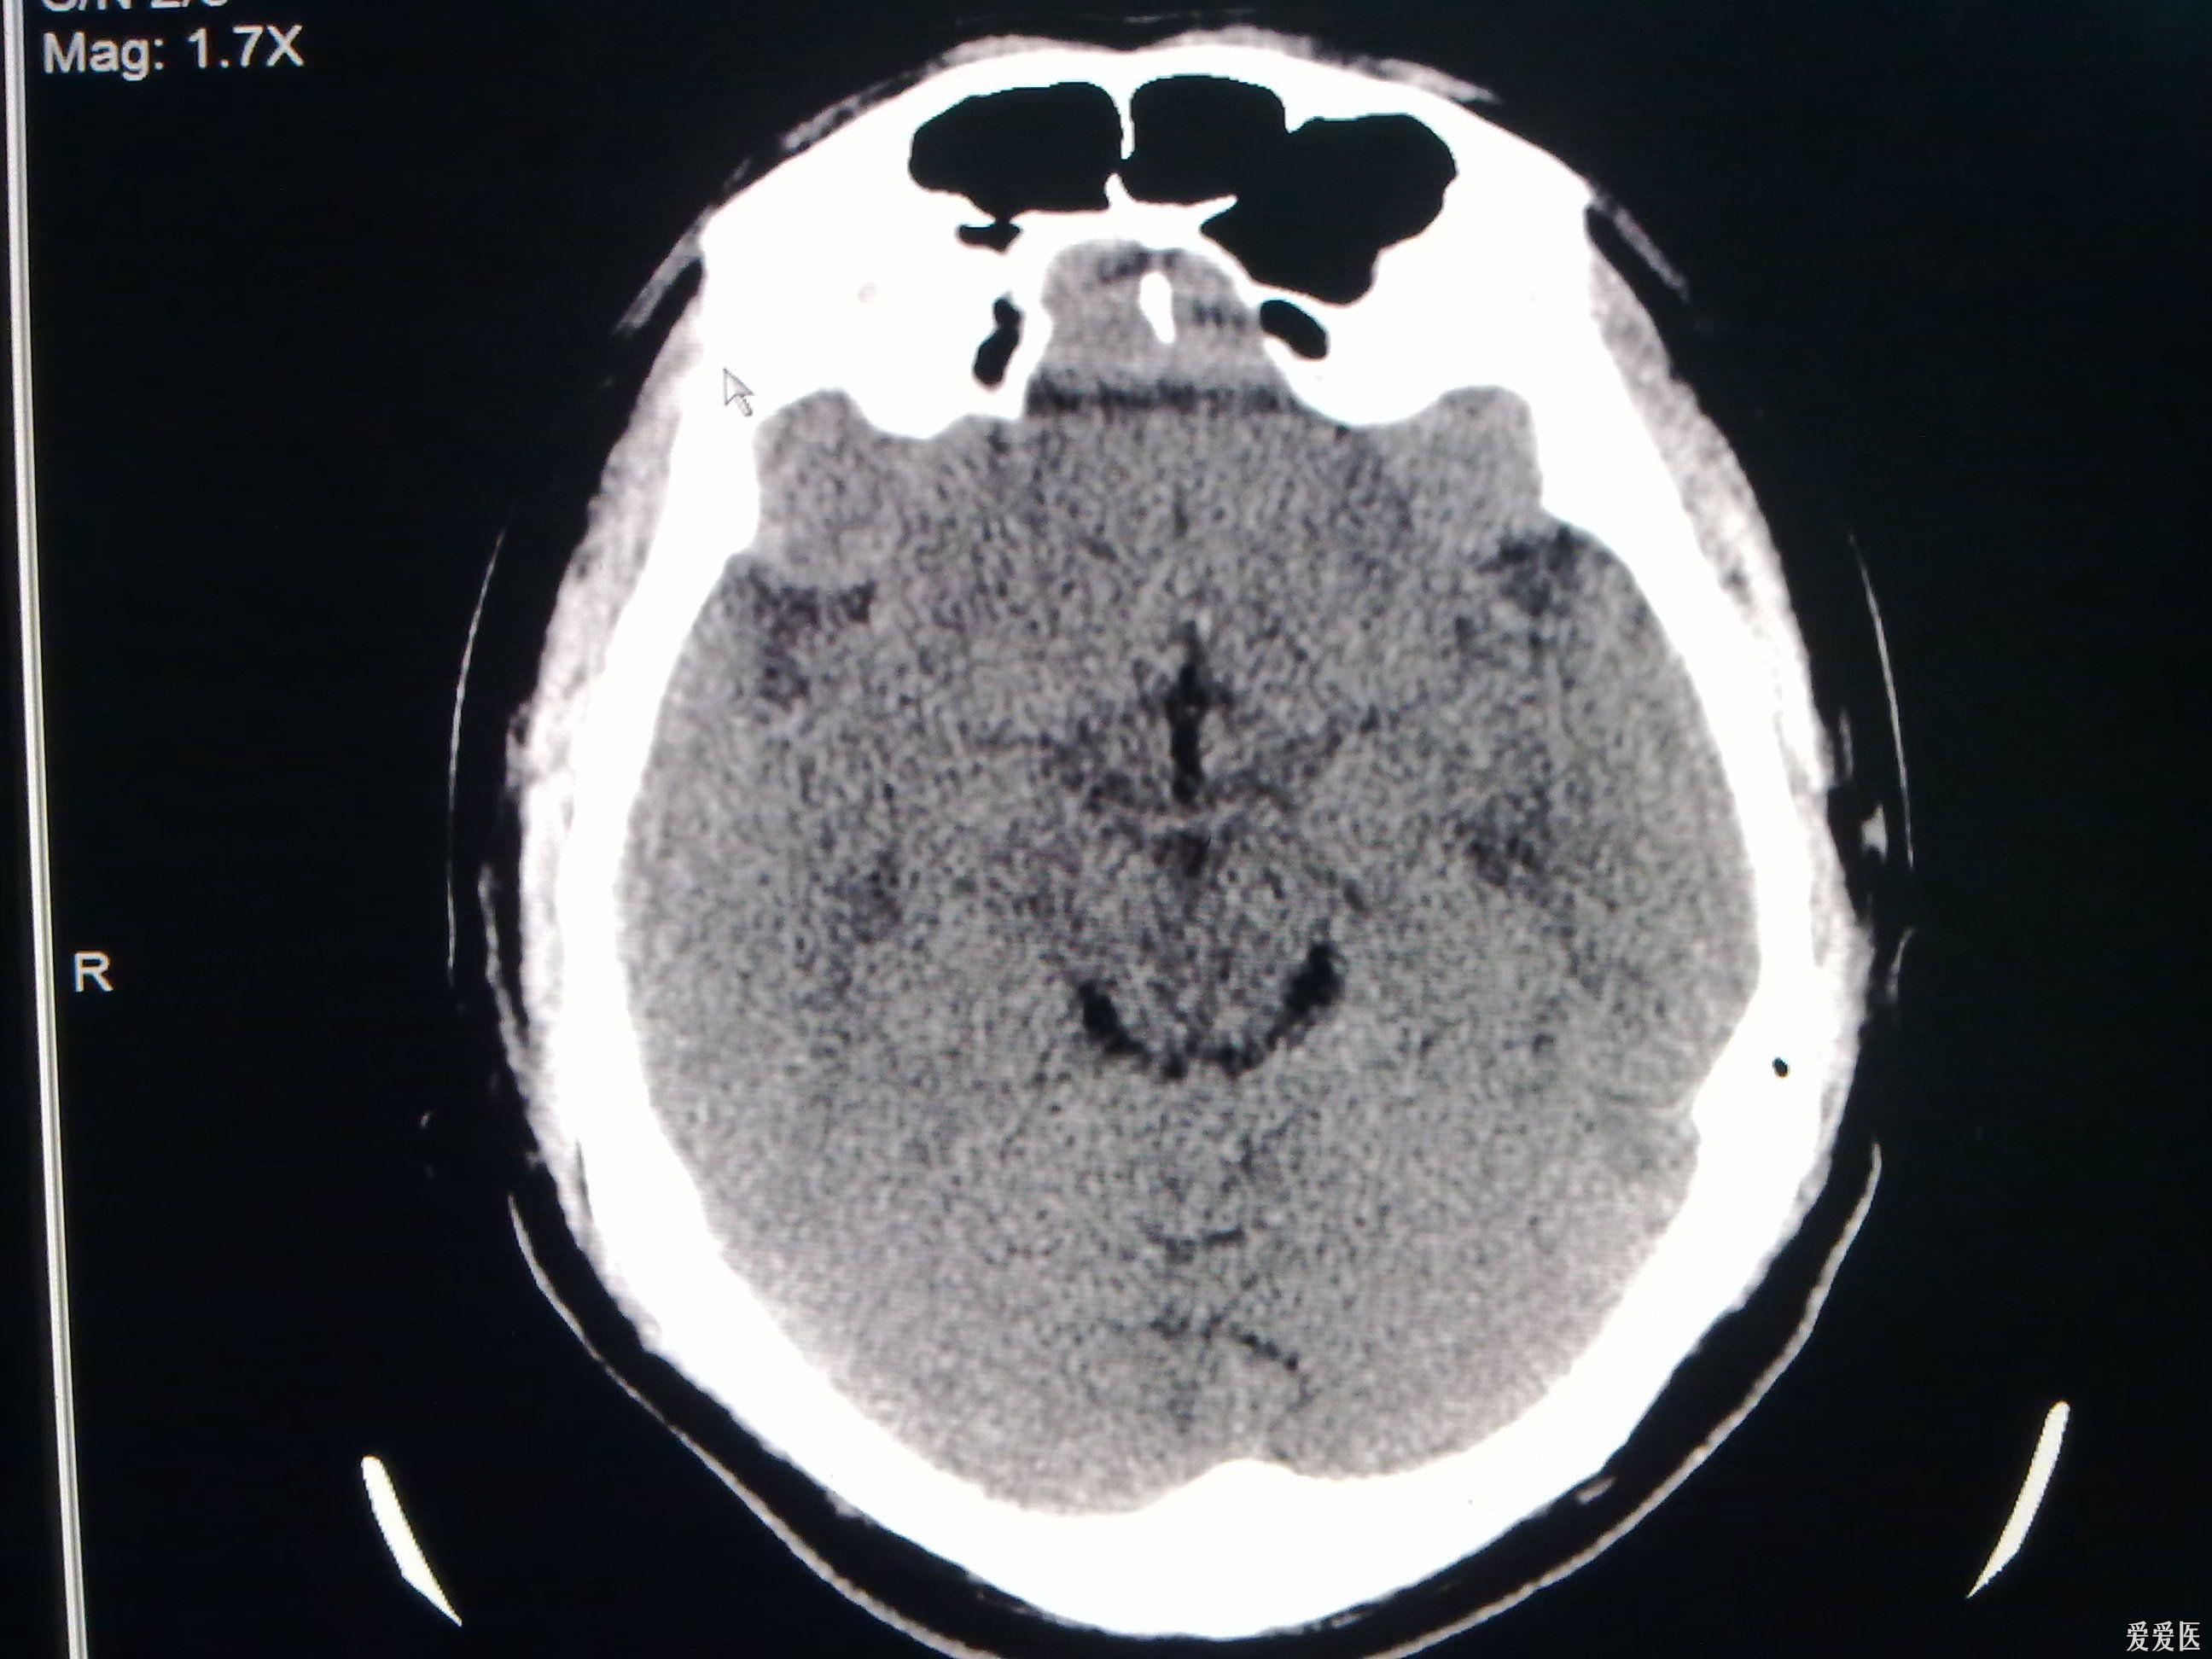

今天做到的病例脑裂畸形

图片尺寸2592x1944

今天做到的病例脑裂畸形

图片尺寸2592x1944

今天做到的病例脑裂畸形

图片尺寸2592x1944

今天做到的病例脑裂畸形

图片尺寸2592x1944